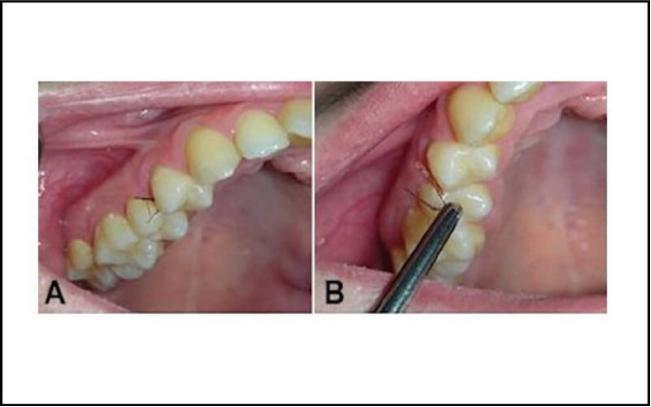

他们的发现发表在《口腔外科学、口腔医学、口腔病理学和口腔放射学》杂志上,记录了这名女子奇怪并反复出现的症状。2009年,她第一次寻求帮助,当时她的上门牙后面不断长出睫毛状的毛发。

起初,这似乎奏效了。有好几年,她牙上的毛发都没有再长出来,但在2015年,毛发又长出来了,而且扩散到了下巴和脖子。

这位当时25岁的女子在毛发长出来之前已经停止服用避孕药,所以医生们只是像以前一样采取了*管双**齐下的方法:医生给她开了药物来平衡她的激素水平,还给她做了手术,并让她一年后再来。但在接受这些治疗后,她的牙龈长出了更多的毛发。